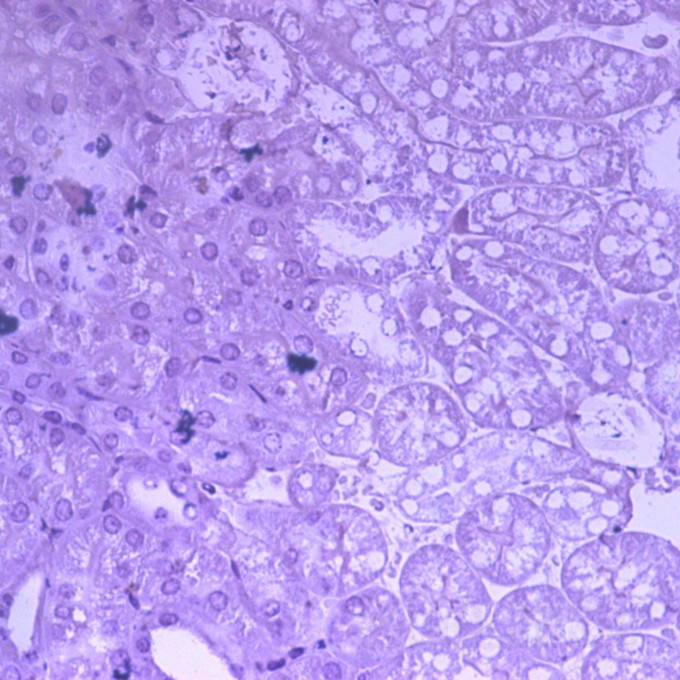

做肾组织 切片的免疫组化时,为何用苏木素染不上细胞核的颜色?而其他的组织,包括肠子,都能染得很漂亮。